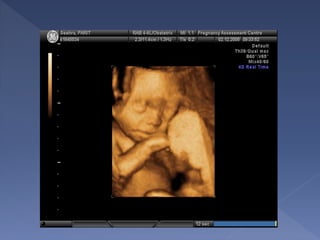

two-dimensional ultrasound (2D)

three and four-dimensional

ultrasound (3D/4D)